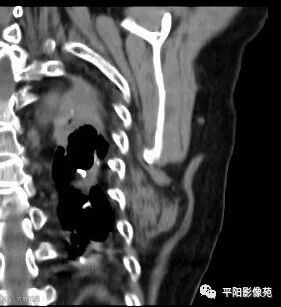

两例患者均为左侧肩胛下实性软组织肿块,边缘模糊,质软,内为肌肉样密度及脂肪密度,以肌肉样密度为主。

CT:边界模糊,与肌肉相似的密度,病变内部可见点状、条状脂肪密度,增强扫描轻度强化或无强化。

综合其好发部位及影像特征可以确诊。